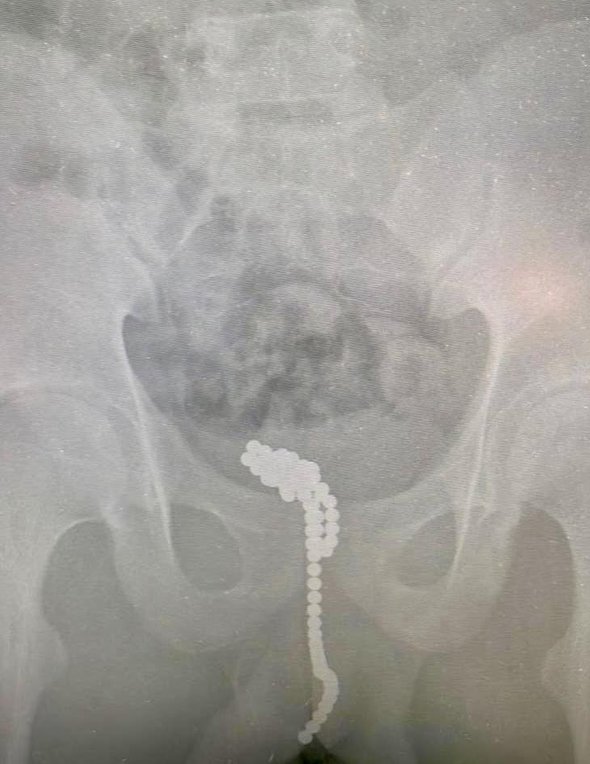

Хирургическим путем магниты извлекли через небольшой разрез в мочевом пузыре. Контрольный рентген подтвердил, что инородных тел в мальчике не осталось.

фото: t.me/minzdravmosreg